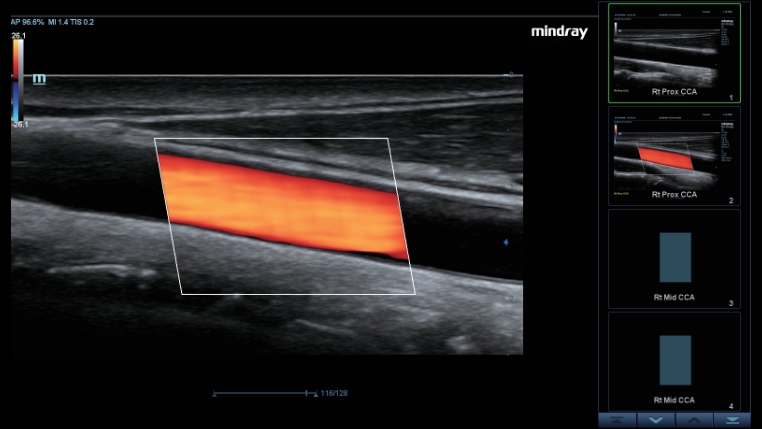

Ak?ll? Takip

Ak?ll? Takip, yaln?zca tek dokunu?la ?al??arak, vaskÞler g?rÞntÞleme i?in h?zl? ve ak?ll? optimizasyon sa?lar. Otomatik takiple, Renk, GÞ? ve PW spektrumunu optimize edebilir ve zaman alan ad?mlar? azaltabilir. Bu nedenle, vaskÞler muayene i? ak??? optimum g?rÞnÞmle basitle?tirilir.